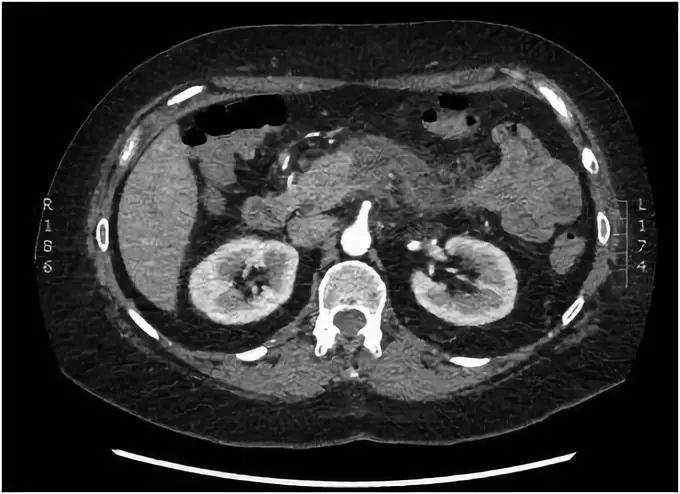

实验室检查显示,白细胞计数为13.65×109 /L(正常4-11×109 /L),C反应蛋白为67 mg/L(正常<5 mg/L),脂肪酶为809 U/L(正常20-210 U/L)。血红蛋白、肝功、钙和血脂均在正常范围。腹部CT扫描显示胰腺体炎症,胰周绞合,周围少量液体积聚,符合急性胰腺炎表现(图1)。同时,没有发现胆总管结石以及扩张,也没有气腹迹象。胰腺未见任何解剖结构上的异常。

图1 腹部CT提示胰腺周围有明显的炎性绞合,与胰腺炎表现一致